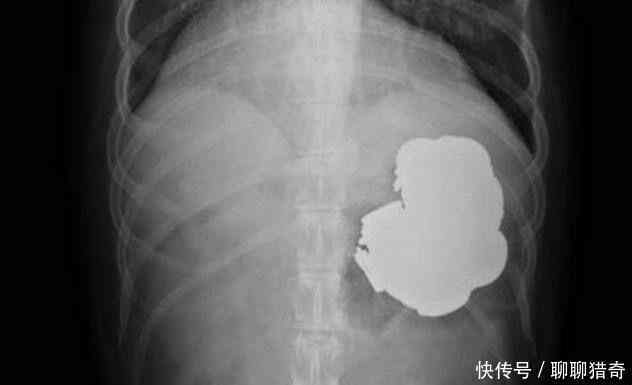

看完后女子和医生当场都愣住了,因为在女子的体内居然发现大片的铁屑,很难想象这些东西是怎么进入到女子的体内,医生表示也是第一次见到这种情况。

随后经过长达四个小时的手术,女子终于脱离危险,但也要继续住院以便观察,怕出现什么后续情况。大家认为这些铁屑是怎么进入女子体内的呢?